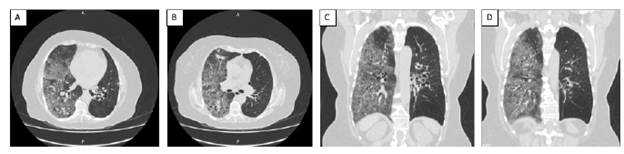

Al día siguiente, fue llevada a tomografía computarizada (TC) torácica que confirmó la presencia de opacidades alveolares difusas con patrón en vidrio deslustrado hacia el lóbulo medio e inferior del pulmón derecho (Ver Figura 2) que, a pesar de ser un hallazgo inespecífico, dado el contexto clínico y en ausencia de elementos sugestivos de infección activa (neumonía adquirida en la comunidad), expresión de autoinmunidad (se descartó hemólisis, no había compromiso cutáneo o renal) o alteraciones estructurales evidentes en vía aérea superior (sin epistaxis ni sangrado espontáneo en mucosa oral), se interpretó como un probable cuadro de hemorragia alveolar de distribución unilateral representando un escenario potencialmente fatal de sangrado mayor, por lo que se añadió inmunoglobulina venosa (IVIg 1g/kg/día IV durante dos días), seguida de dexametasona 40 mg/día IV durante 4 días. Igualmente, se solicitaron estudios microbiológicos y moleculares en esputo, todos negativos.

Figura 2 A y B Cortes axiales de TC de tórax; C y D Cortes coronales de TC de tórax. Todas muestran opacidades alveolares difusas en vidrio esmerilado en el lóbulo medio e inferior del pulmón derecho; bronquiectasias en el lóbulo inferior de ambos pulmones y fibrosis en hemitórax derecho con bandas pleuroparenquimatosas en el lóbulo superior.